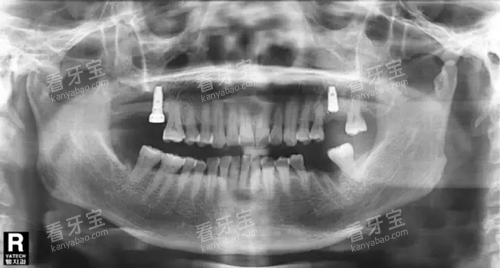

同时,医院还配备了较高的口腔种植设备,如口腔 CT 等,为种植手术的成功提供了有力的维持。